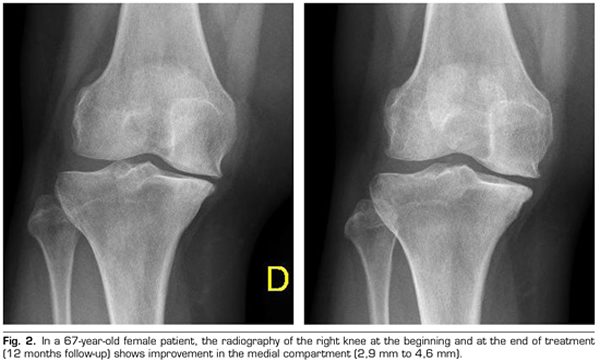

Regarding the radiological variables, when evaluating 53 out of the 115 patients who completed one year of follow-up after ozone treatment, it was observed that the internal compartment increased significantly by 4.12 ± 1.41 mm to 4.4 ± 1.35 mm (p = 0.0008) and the external compartment increased from 6 ± 1.37 to 6.16 ± 1.4 mm (p = 0.0753) (Table II). Two clinical cases are presented as a sample of the radiological change in the internal and external compartments (Figures 2 and 3).

After a year of follow-up with radiological controls on 53 out of the 115 patients in the study, ozone (O2-O3) has been able to increase the minimum joint space of the medial compartment (from 4.12 to 4.44 mm) and the lateral compartment (from 6.0 to 6.16 mm), reversing knee osteoarthritis in our case series. This finding suggests the disease modifying effect of ozone (O2-O3) on knee osteoarthritis, findings that is consistent with the recently reported by Fernández-Cuadros et al. (9).